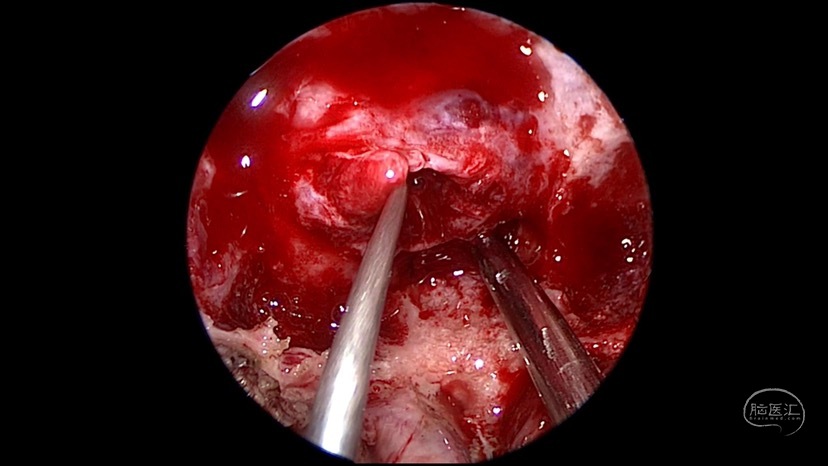

神经内镜辅助手术治疗垂体瘤卒中一例

图片尺寸792x656